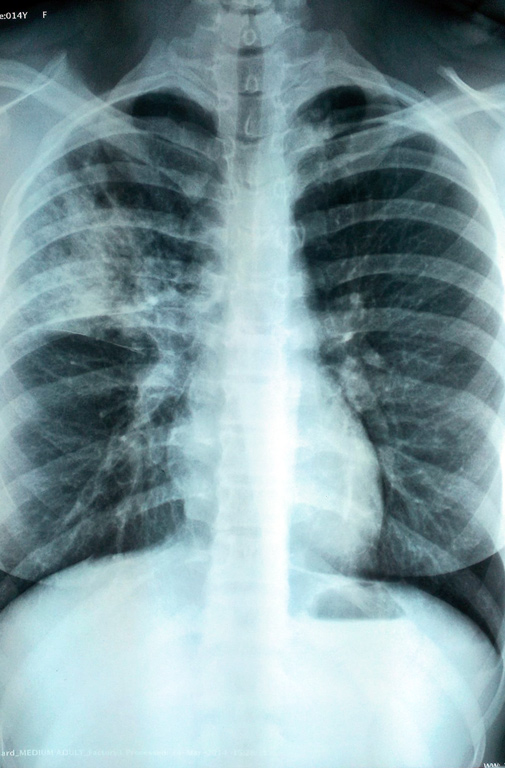

Инфекционные заболевания, это хороший пример того, что государство должно очень сильно регулировать свободы. В адрес туберкулёзников, сифозников и приравненных к ним гражданам, например отказывающимся от прививок, должны применяться правила как к преступникам. То есть соответствующие лагеря с принудительной медициной и обязательной работой, для отрабатывания затраченных на них денег.

В адрес туберкулёзников, сифозников и приравненных к ним гражданам, например отказывающимся от прививок, должны применяться правила как к преступникам.Я являюсь сторонником прививок. Но в данном случае поработаю адвокатом дьявола, так как на мой взгляд, обсуждающие не осознают один простой момент - в случае прививок пользу получает общество, а возможный вред от факта прививки - индивидуум. Т.е. по сути перед родителями стоит выбор - вероятность вреда от прививки своему ребенку или вероятность вреда и окружающим, и ребенку от болезни. При этом всегда есть шанс, что не заболеет, и прививка не всегда тут играет ведущую роль (именно для индивидуума. а не для общества - для общества нужна максимальная доля привитых а вот от шанса на побочку никуда не денешься - он зависит только от факта прививки. С учетом криворукости некоторой доли медперсонала и качества некоторых прививок этот выбор становится еще тяжелее. А уж если знать например про остеомиелиты, БЦЖиты и холодные абсцессы от БЦЖ (и их доля прилична от доли всех прививок БЦЖ то ситуация становится далеко не такой однозначной. На мой взгляд, общество должно правильно компенсировать вот эту тяжесть индивидуального вреда, и пока оно этого не делает - от прививок будут шарахаться. Под компенсацией я подразумеваю прежде всего честную позицию здравоохранения (сейчас позиция -максимально замять и наказать огнем по площадям нормальную возможность реабилитации для тяжелых случаев. Ну и пропаганду-пропаганду-пропаганду.

В отношении противотуберкулезных мероприятий у детей здравоохранение в лице как врачей, так и НПА ведет себя крайне неконструктивно. Пример - есть ребенок с уже зафиксированной гиперреакцией на Манту, ничего не имеющей общего с инфицированием. Вопрос - нахрена ему ежегодно делать эту Манту, а не диаскин по умолчанию, провоцируя раздувание у ребенка на пол-руки и истерику мамы? Ответ - потому что так положено по бумажке, а не по медицинской логике. Итог -мама обоснованно шарахается от Манту, диаскин ей пратически недоступен, итог - ребенок вне наблюдения. Хорошо только бюджету-на диаскин не потратится.

Еще ситуации - Манту должна делаться внутрикожно, но из-за криворукости медперсонала её часто ставят неправильно, что дает опять-таки её неинтепретируемость как положено, и кучи детей вкупе с семьями имеют многонедельный геморрой по подтверждению того, что ты не верблюд от криворукости медсестер. Итого многие мамы (и я в том числе) предпочитают делать Манту там, где её делают правильно именно из клинических и рациональных соображений. Но не за деньги сейчас это ГИГАНТСКИЙ геморрой. Итого подобное ответственное и внимательно отношением мам не просто не поддерживается, а всячески гнобится. И куда думающим мамам податься? Это я, проживая в Москве и имея финансовые возодности, могу позволить себе платно сделать сыну и 2. и 3 типа тестов для перероверки в удобное для меня время. Менее обеспеченные себе это позволить не могут, а ба в провинции и платно, и бесплатно только опция криворукости может быть без вариантов, и как закономерный итог - марш строем к фтизиатру просто так. Итог-мамы шарахаются как от огня от Манту, дети не под наблюдением.

Еще известный выверт медперсонала - мерить гиперемию, а не папулу как положено. Элементарнейшая вещь, но сколько крови вот эта ошибка массово попила всем - это не передать. И её следствие- родители вообще перестают доверять Манту, так как она из года в год оказывается ложно положительной, причем не из-за сущности теста, а из-за того, что тупо не то померили. А эта ложноположительность означает необходимость рентгена ребенка, анализ крови ему, рентген всей семьи, визит к фтизиатру и т.д. Это отборный геморрой на ровном месте на несколько недель просто так.

Короче, я к сожалению, не вижу от государства конструктива в эту сторону. Я согласна с тем, что ужесточили СанПиНы. Но их мало ужесточить - нужно поощрять адекватное поведение, а не продолжать его гнобить.